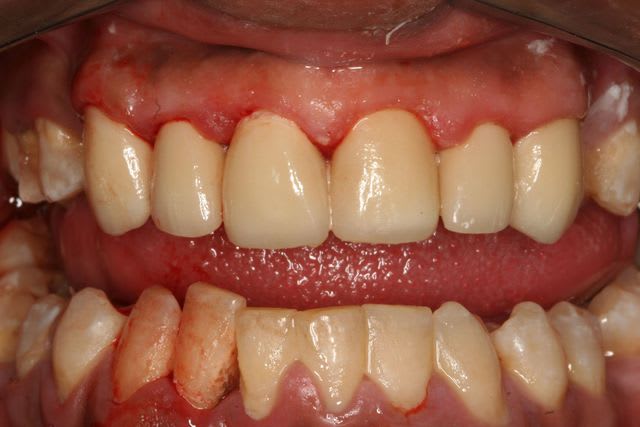

Magnifique ! intégration biologique au top dans un parodonte en tiers payant lui aussi. Ajustage exceptionnel sur 11 qui ne rentre pas à fond. Comblé au ciment de scellement. Les bulles c'était sur 21 22.